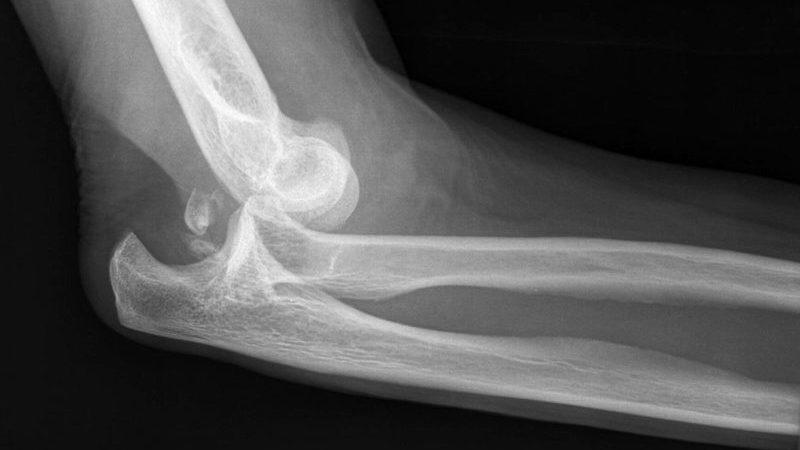

Врачам обычно не составляет труда определить вывих, так как он сопровождается характерными признаками. При осмотре пациента можно заметить, что область повреждения значительно отекает. Также наблюдаются изменения в анатомическом строении локтя. Одним из наиболее ярких признаков, указывающих на вывих предплечья, является «пружинистая подвижность». Этот симптом проявляется при попытках движения больной рукой.

Тем не менее, бывают ситуации, когда диагностика становится сложной. Это может произойти, если до визита к врачу были приняты обезболивающие препараты. Они способны почти полностью скрыть симптомы. В таких случаях на помощь врачу приходит рентгенография. После выполнения рентгеновского снимка специалист сможет установить точный диагноз. При необходимости может быть проведена и контрастная рентгенография.